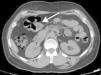

2Clinical caseA 49-year-old female was admitted to the Gastrenterology department for an elective colonoscopy. The patient had left-sided ulcerative colitis in clinic remission (S0, Montréal classification of disease activity). There was no family history of colonic tumors or neurofibromatosis. On colonoscopy, a subepithelial mass (3.0cm-sized) with normal overlying mucosa in the ascending colon was found (Fig. 1); the remaining colon was normal (ulcerative colitis in endoscopic remission). There was a report of a previous normal colonoscopy (three years ago). Abdominal examination revealed no abnormality. Contrast-enhanced abdominopelvic computed tomography showed a 2.9cm-sized well-circumscribed mass contiguous with intestinal wall that protruded intraluminally and exhibiting homogenous enhancement (Fig. 2). As the lesion was deeply located in intestinal wall and due to uncertainty of a definitive diagnosis, a right hemicolectomy and lymph node resection was performed. Histopathological evaluation was compatible with schwannoma. The mass was composed of benign spindle cells arranged in bundles, with dense distribution of nucleus forming palisades in dense fibrillar stroma and mitotic count was low (Fig. 3). Immunostaining revealed strong positivity for S100; muscle markers, vimentin, CD34 and KIT (CD117) were negative (Fig. 4). The lymph nodes were normal. The patient's postoperative evolution was uneventful.